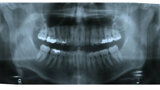

ClearCorrect treatment of crowding